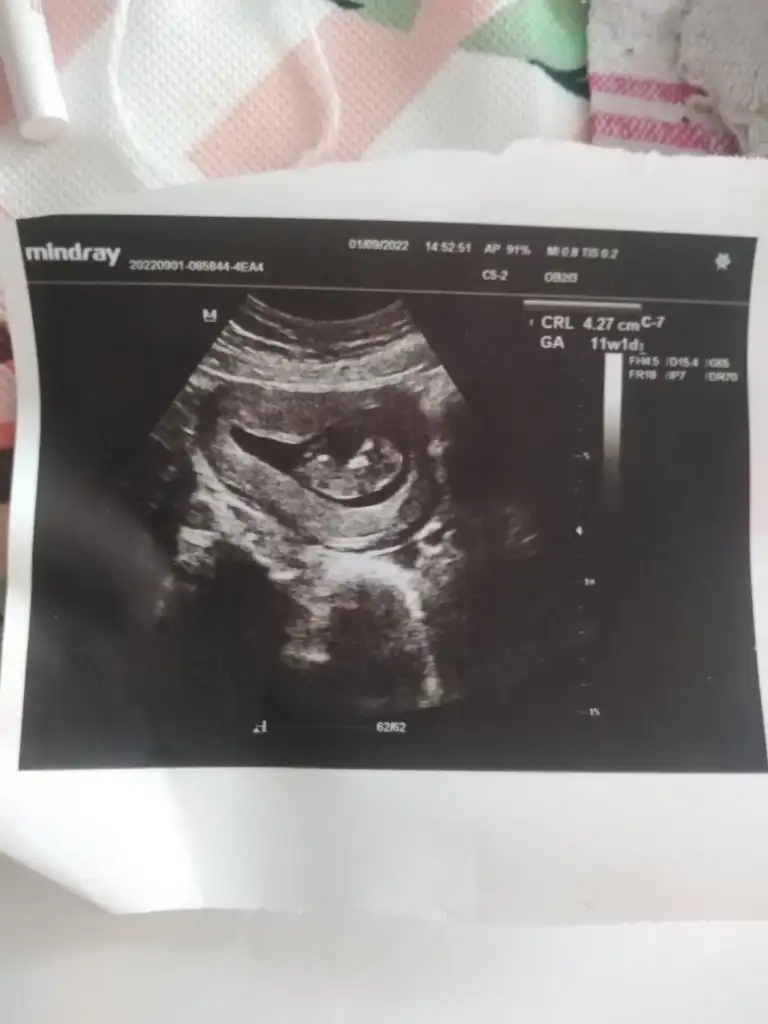

Merhaba bana da tahminde bulunurmusunuz lütfen 🥰🙏 10+4 ve 10+6 karindan ultrason fotolari. 1. Resimdekini pipi zannetmistim meğer ayağiymiş 😅🙈

20220906_175540.webp 20220905_160108.webp